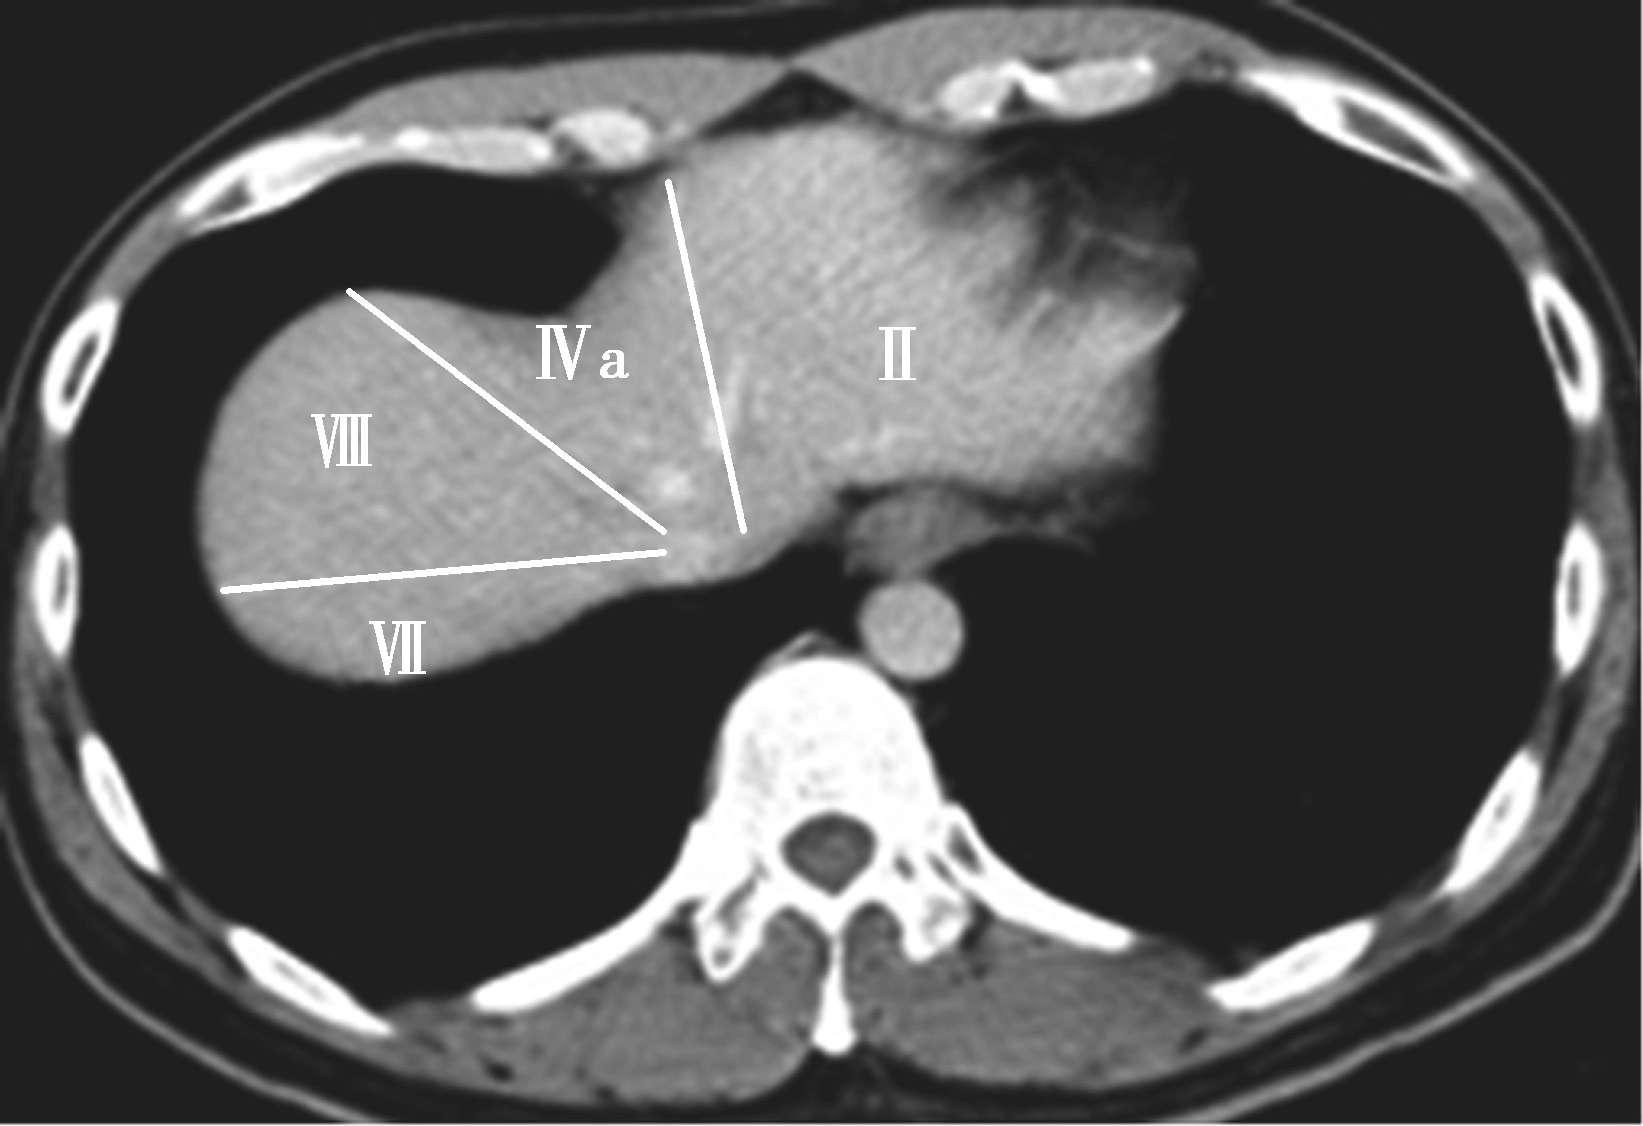

(3)肝8段划分法(图5-21-35):

Couinaud根据门静脉及肝静脉的分布将肝脏分为8段,门静脉分布于肝段内,肝静脉分布于肝段间。8分段法是临床外科和影像最为常用的分段法。以肝中静脉为界分为左、右半肝;以肝左静脉为界将左半肝分为左内(Ⅳ段)和左外叶(Ⅱ段+Ⅲ段);左外叶以门静脉左支为界水平分为上(Ⅱ段)下(Ⅲ段)两段;以肝右静脉为界分右半肝为前叶(Ⅷ段+Ⅴ段)和后叶(Ⅵ段+Ⅶ段);以门静脉右支为界将右肝横向分为上下两段分别为右前上段(Ⅷ段)、右前下段(Ⅴ段),右后下段(Ⅵ)和右后上段(Ⅶ段);肝尾状叶为单独一段(Ⅰ段)。

图5-21-35 肝8段划分法示意图